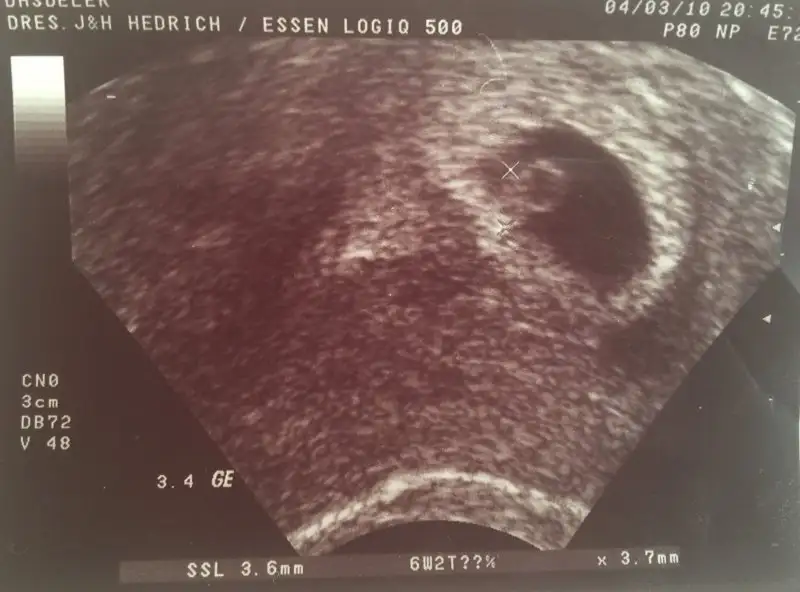

İlk hamileliğimdeki ultrason resimlerine bakıyordum buraya da eklemek istedim belki merak eden olur kaçıncı haftada nasıl görünüyor diye

Bu 6 hafta 2 günlük

IMG_2987.webp